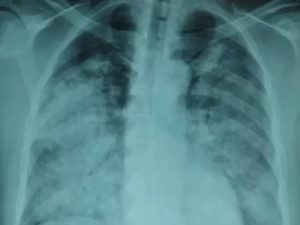

Признаки пневмонии на рентгеновском снимке во многом зависят от формы заболевания и его стадии, а также от локализации патологического процесса. Если исследование показало признаки пневмонии, необходимо как можно скорее приступить к лечению – запущенный патологический процесс опасен не только для здоровья, но и для жизни человека.

Первый признак пневмонии на рентгеновском снимке – появление очагов затемнения с неровными контурами в разных частях легкого, которые могут иметь разный размер, от 3-4-х до 12 мм.

Тени различают по внешнему виду (круглые, овальные кольцевидные) и интенсивности окраски – чем темнее пятно, тем сильнее выражен патологический процесс.

При поражении лимфатических узлов и нарушении кровоснабжения органа могут наблюдаться изменения корней легких, а если болезнь затронула плевру – нарушение в рисунке куполов диафрагмы. В остальном проявления пневмонии зависят от стадии, формы и клинических особенностей заболевания:

- Очаговая форма. На рентгене отображаются небольшие (1-1,5 см) тени со слабой или умеренной интенсивностью окраски, неоднородной структурой и нечеткими границами. Очаги поражения могут быть единичными или множественными, а в некоторых случаях они сливаются в одно большое пятно. Корни легких расширены, причем нарушения нормального рисунка органа могут сохраняться в течение нескольких дней после выздоровления.

На фото видны признаки пневмонии:

- светлые полости;

- размытые контуры воспалительных очагов;

- затемнения за счёт уплотнений.

Сравнение здоровых и воспаленных легких на рентгенографии Абсцесс лёгких на рентгеновском снимке Абсцесс при левостороннем верхнедолевом воспалении лёгких Очаговая пневмония Крупозная пневмония на рентгене Казеозная пневмония